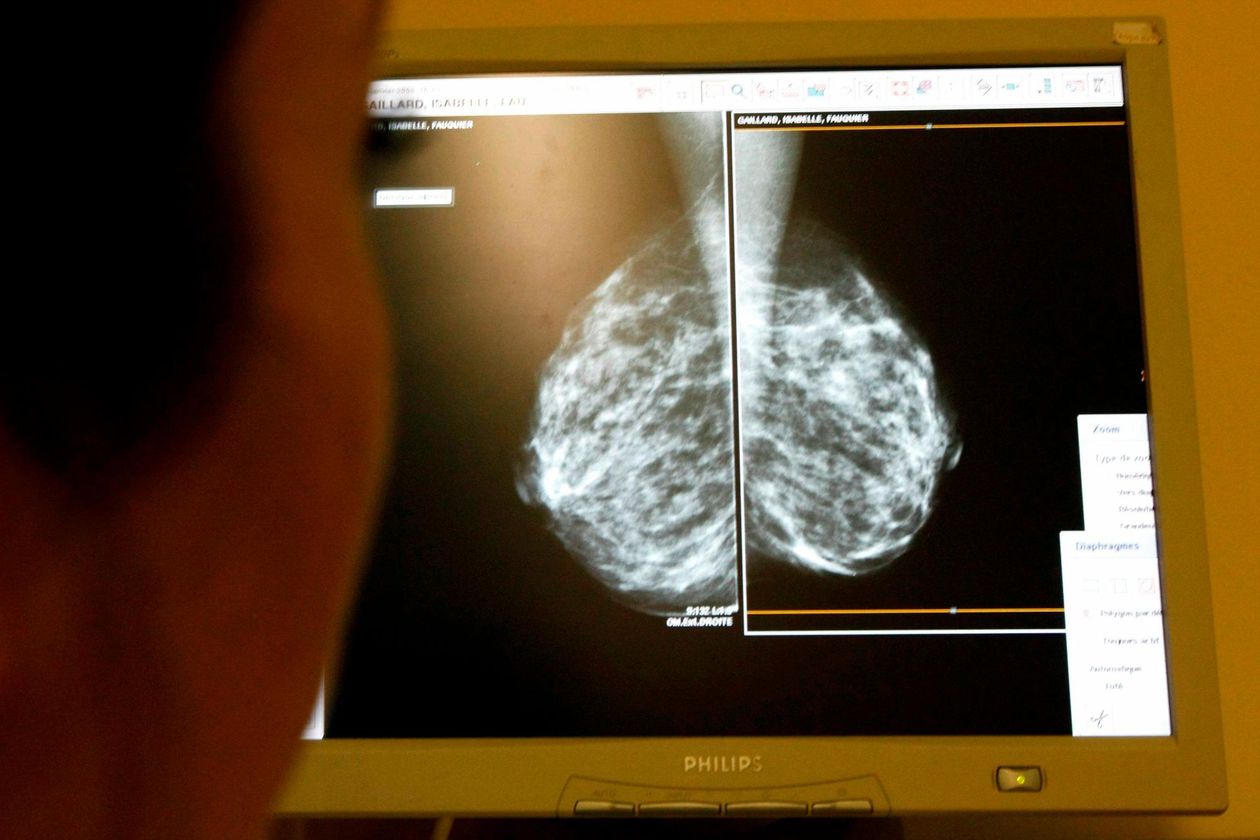

Foto: Reuters

Campeche es la entidad con menor tasa de mortalidad por cáncer de mama a nivel nacional, informó Nicolás Briceño Ancona, director del Centro Estatal de Oncología (CEO), donde han atendido a más de 400 pacientes en los últimos cinco años.

Mientras que a nivel nacional el porcentaje ronda en 17.19 por ciento por cada 100 mil mujeres mayores de 20 años los índices de cáncer de mama, en Campeche esta tasa es de 5.8 por ciento por cada 100 mil mujeres mayores de 25 años.

De los 442 pacientes que atendieron del 2015 y hasta el presente año más de 50 por ciento corresponde a mujeres de la capital campechana; 16 por ciento a pacientes de Carmen; ocho por ciento de Champotón; ocho por ciento de Escárcega; cuatro por ciento de Calkiní y Candelaria, y tres por ciento de Hecelchakán.

Briceño Ancona invitó a las mujeres campechanas a realizarse una autoexploración de manera regular ya que es la única manera de detectar cualquier tipo de irregularidad y darle una atención oportuna, servicio que está cubierto por el seguro catastrófico del seguro popular en el caso de las mujeres que no tienen servicio médico en el IMSS o ISSSTE.